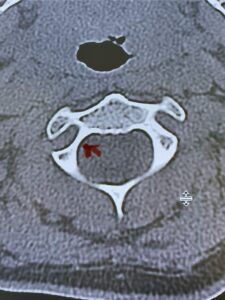

Fig. 2b: Axial CT scan of the brain demonstrating the thickness of the midline keel (red arrow) compared to the more lateral subocciput (red dot) making the keel ideal place for screw fixation

Fig. 6c: Axial cervical CT scan demonstrating a very thin right C2 isthmus (red arrow) compared to left side.